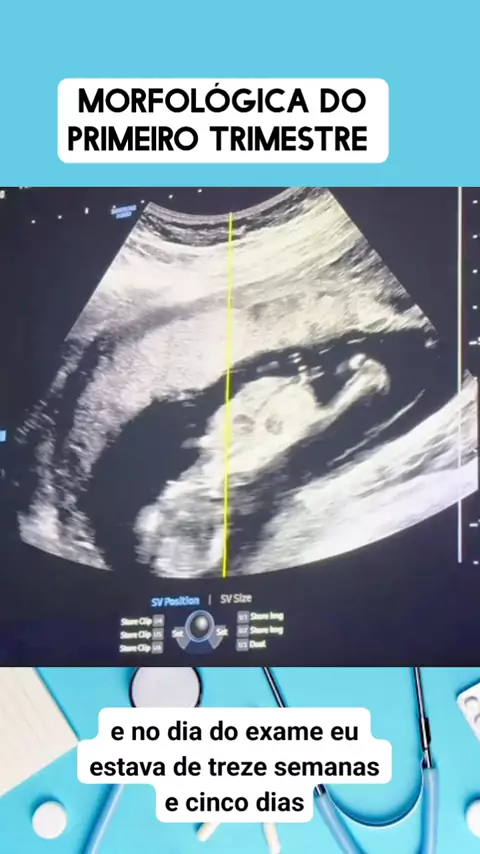

💉MÉDICO EM AÇÃO ✍️

#medico #medicina #Saúde #viraliza